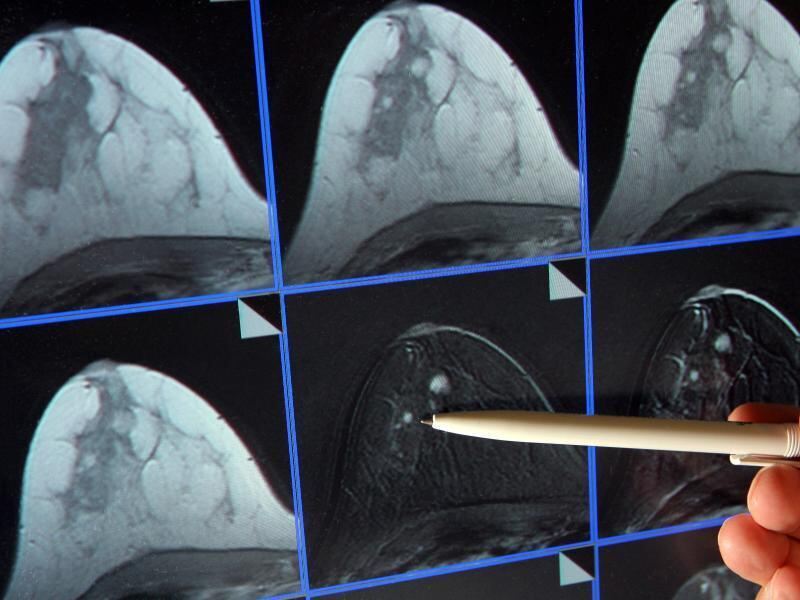

Auf der Bildschirmdarstellung einer Magnetresonanz-Mammographie ist ein winziger Tumor in einer Brust zu sehen. Foto: Jan-Peter Kasper/Archiv